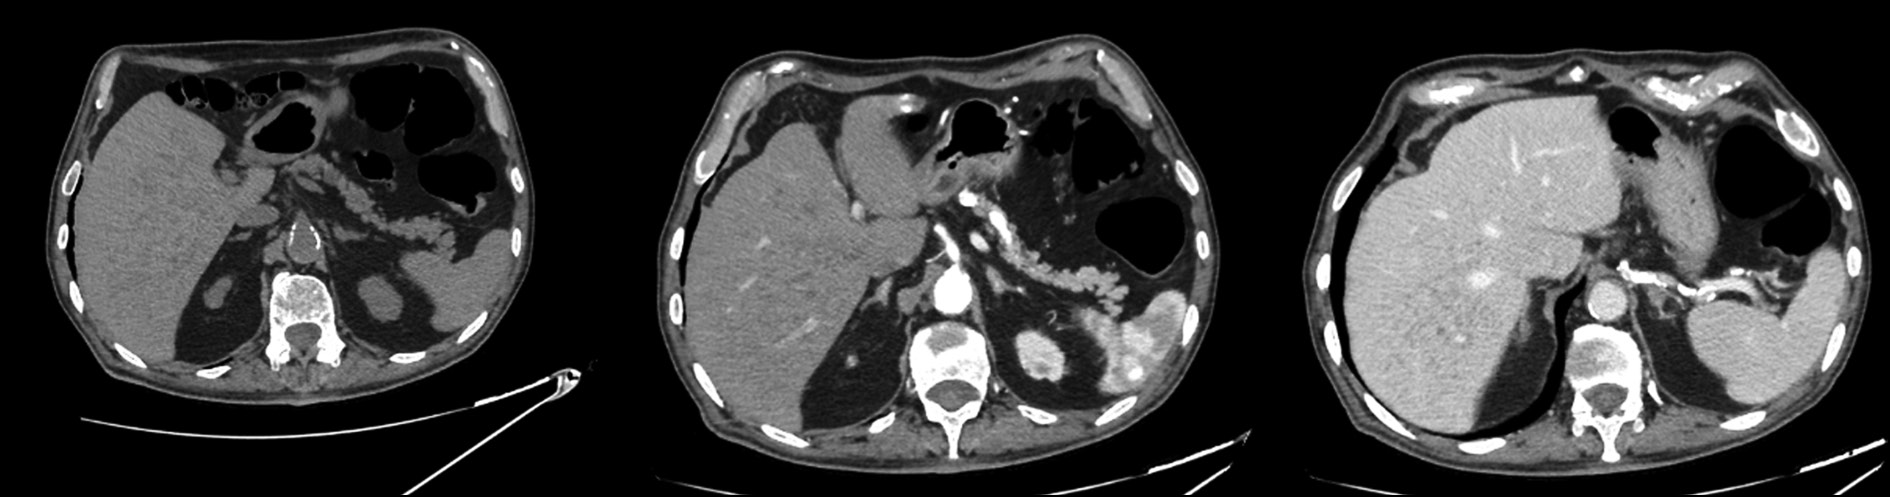

Multiple millimetric disorganized hypodense lesions, both subcapsular and intraparenchymal, were detected incidentally in both hepatic lobes on CT.

After the administration of contrast medium, enhancement of lesions was not observed (Fig. 1).

Fig. 1. Axial CT image: hypodense lesions without significant contrast enhancement in the arterial and venous phases.